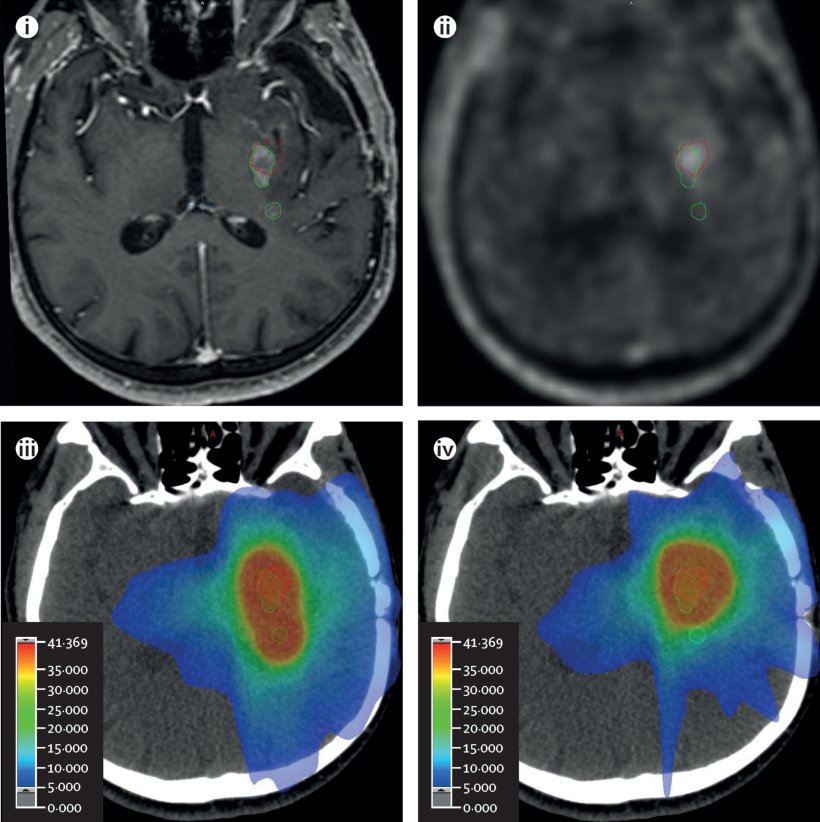

Bildquelle: Grosu AL, Weber WA, Graf E et al., Lancet Oncology 2026 (CC BY 4.0)

In der von der Deutschen Krebshilfe geförderten GLIAA-Studie (NOA-10-Studie bzw. ARO-2013-01) wurden von 2013 bis 2021 insgesamt 200 Patientinnen und Patienten mit rezidiviertem Glioblastom aus 15 teilnehmenden radioonkologischen Zentren eingeschlossen. Alle Patienten erhielten sowohl ein FET-PET als auch ein MRT, aber zur Bestrahlungsplanung wurde entweder das FET-PET oder MRT (jeweils bei 100 Patienten) eingesetzt. Die mit den beiden Verfahren ermittelten Bestrahlungsvolumina waren sehr ähnlich, im Median 7,2 ml in der FET-PET-Gruppe und 6,1 ml in der MRT-Gruppe; allerdings waren die so ermittelten Volumina nicht vollkommen identisch mit nicht-überlappenden Anteilen von 3,2 bzw. 2,7 ml. Die Behandlung war eine stereotaktische fraktionierte Strahlentherapie des Tumorrezidivs mit 13 Fraktionen mit jeweils 3 Gy. Bezüglich des medianen progressionsfreien Überlebens (4,0 bzw. 4,9 Monate) und der lokalen Tumorkontrollrate nach einem Jahr (22% versus 20%) bestanden keine signifikanten Unterscheide zwischen der Planung mit FET-PET oder MRT. Die Re-Bestrahlung wurde gut vertragen; die kumulative Häufigkeit von Nebenwirkungen Grad 3 oder höher betrug 12% bzw. 14% für akute Nebenwirkungen und 20% bzw. 16% für relevante Spätfolgen.